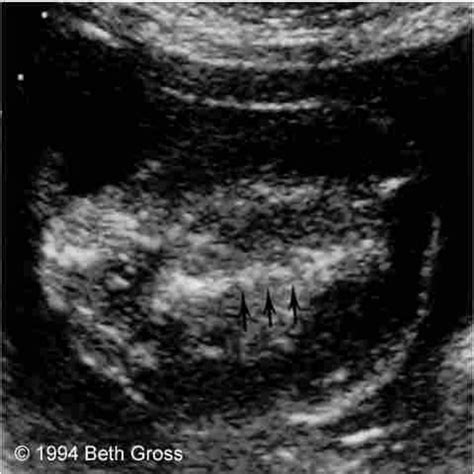

Early diagnosis of TRAP sequence is crucial for managing the condition effectively. Ultrasound examinations are the primary diagnostic tool, typically performed between 10 and 14 weeks of gestation. Key indicators of TRAP sequence include:

• Absence of a heartbeat in the acardiac twin.

• Reverse blood flow from the pump twin to the acardiac twin.

• Abnormal development of the acardiac twin, often characterized by a lack of a functional heart and other organ malformations.

Doppler ultrasound is particularly useful in visualizing the abnormal blood flow patterns characteristic of TRAP sequence. Magnetic Resonance Imaging (MRI) may also be used to provide a more detailed assessment of the twins' anatomy and the extent of the condition.